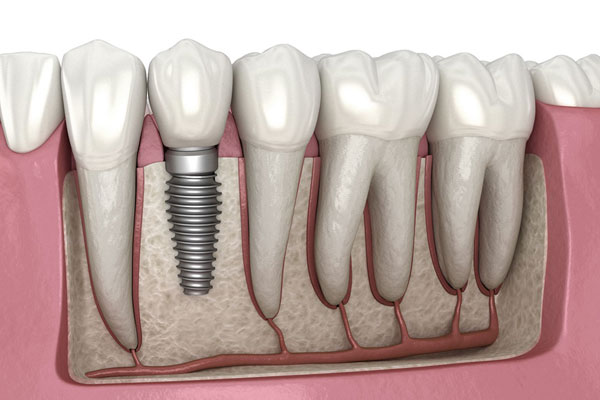

A dental implant is a surgical fixture that is placed into the jawbone and allowed to fuse with the bone over the span of a few months.